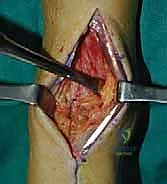

خطوات جراحة تثبيت مفصل الكاحل الأمامي بالتفصيل (Step-by-Step Surgical Procedure)

1. الوضعية والشق الجراحي (Positioning and Incision)

يستلقي المريض على ظهره (Supine position). يتم استخدام عاصبة (Tourniquet) حول الفخذ لتقليل النزيف وتوفير رؤية واضحة. يقوم الدكتور هطيف بإجراء شق طولي أمامي فوق مفصل الكاحل، عادة بين وتر العضلة الظنبوبية الأمامية (Tibialis Anterior) ووتر العضلة الباسطة الطويلة لإصبع القدم